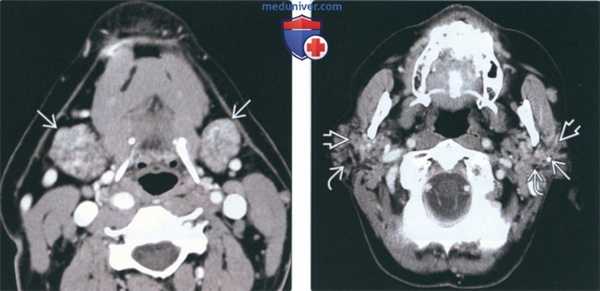

Результаты КТ. Двустороннее увеличение околоушной железы, повышенная плотность и неоднородность структуры на КТ. Точечный кальциноз может диффузно присутствовать в обеих околоушных железах. При контрастировании гетерогенное усиление солидных и смешанных кистозно-солидных образований

(Справа) МРТ Т2ВИ FS, аксиальная проекция. В обоих околоушных железах определяются гипереинтенсивные образования, которые представляют собой кистозное расширение протоков околоушной железы при синдроме Шегрена. Тем не менее, такая МР-картина неотличима от лимфоэпителиальных образований при ВИЧ. (Слева) КТ с КУ, аксиальная проекция. Жировая инволюция обеих околоушных желез, которые имеют многодольчатое строение. В толще желез множественные кальцификаты. Участки отечной железистой ткани, в которой встречаются фрагменты жировой клетчатки и кальцификаты, характерны для синдрома Шегрена.

(Справа) КТ без КУ, аксиальная проекция. Определяется увеличение правой околоушной железы с повышением ее плотности. Такие изменения характерны для воспалительного процесса. И хотя при синдроме Шегрена страдают обе околоушные железы, при обострении может поражаться и одна железа.

3. КТ при синдроме Шегрена околоушной железы:

• Двухстороннее увеличение крупных слюнных желез

• Возможны точечные кальцинаты в крупных слюнных железах

• Множественные милиарные кистозные или солидные очаги в железе

(Слева) На аксиальной КТ с КУ определяются признаки СШ с поражением обеих поднижнечелюстных желез, имеющих неоднородную, «пятнистую» структуру. Правая железа слегка увеличена.

(Справа) На аксиальной КТ с КУ определяется выраженная неоднородность структуры околоушных желез, выглядящих патологически измененными, с наличием мягкотканного компонента, разделенного областями, выглядящими более кистозными. Также визуализируются небольшие кальцинаты.

2. КТ околоушной железы при синдроме Шегрена:

• КТ без контрастирования:

о Симметричное увеличение околоушных желез с повышением их плотности, структура желез неоднородная

о Точечные кальцификаты, рассеянные по обеим железам

• КТ с КУ: